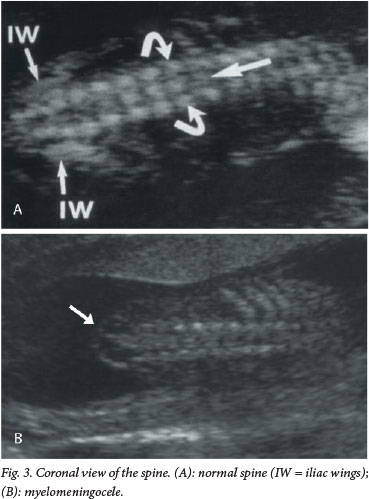

The current recommendation for prenatal screening for fetal abnormalities is that all women be offered an anatomy scan at 18 - 23 weeks' gestation, which consists of a detailed anatomical survey of the different structures of the fetus. The spine is examined systematically from top to bottom in the sagittal, coronal and transverse planes (Figs 1 - 3). Intactness of the vertebrae is assessed, as well as evidence of a sac-like protrusion. Adequate visualisation is dependent on the quality of the machine, the body mass index of the patient, and the position of the fetus. A fetus lying spine down and very close to the uterine wall may make imaging of the spine difficult. In addition, experience of the operator is an important factor.